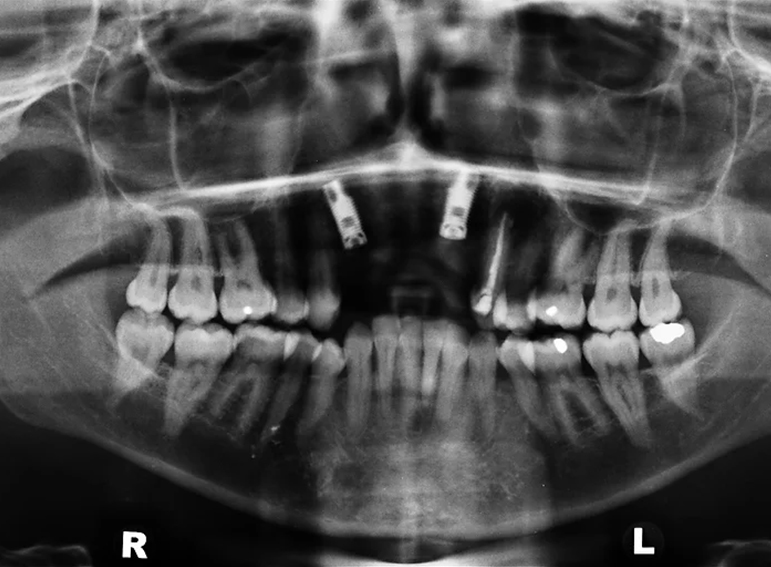

Oral rehabilitation after a road traffic accident.